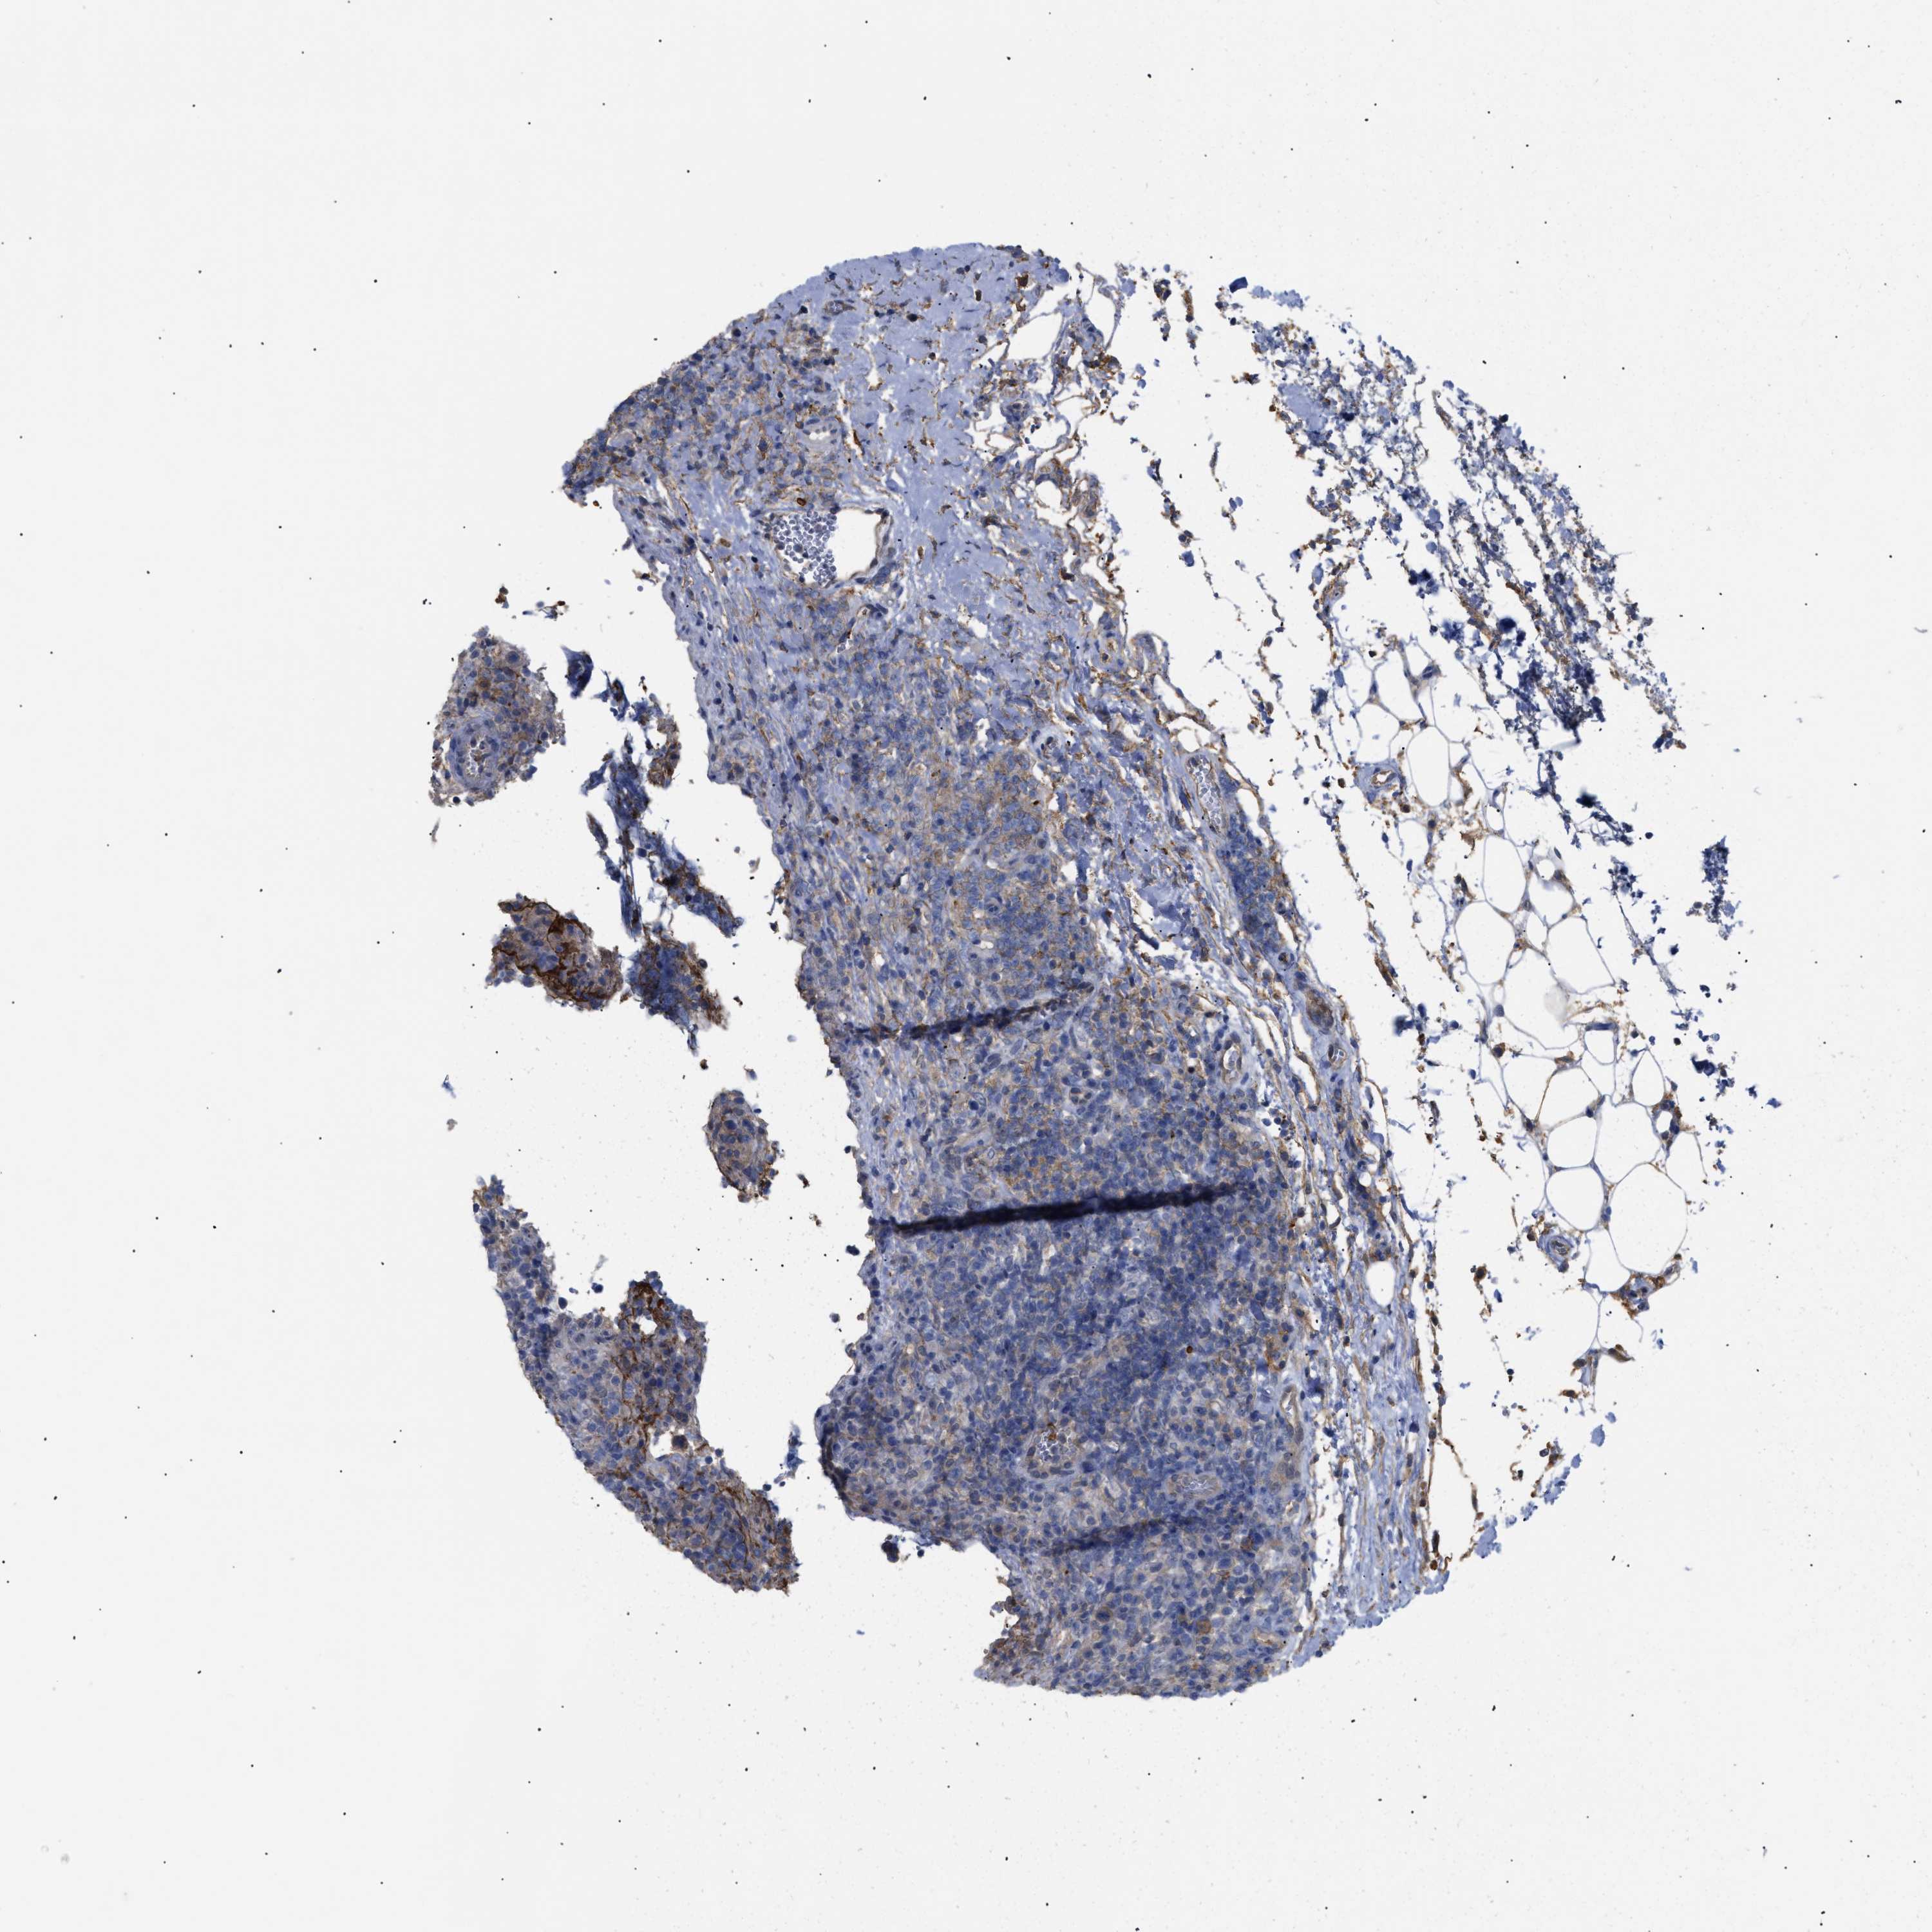

LYMPHOMA - Protein expressioni

A mouse-over function shows sample information and annotation data. Click on an image to view it in a full screen mode. Samples can be filtered based on level of antibody staining by selecting one or several of the following categories: high, medium, low and not detected. The assay and annotation is described here.

Antibody stainingi

Antibody staining in the annotated cell types in the current human tissue is reported as not detected, low, medium, or high, based on conventional immunohistochemistry profiling in selected tissues. This score is based on the combination of the staining intensity and fraction of stained cells.

Each image is clickable and will lead to virtual microscopy that enables deeper exploration of all samples and also displays staining intensity scores, fraction scores and subcellular localization as well as patient and tissue information for each sample.

Antibody HPA007393

Antibody CAB005076

Antibody CAB017560

Staining

High

Medium

Low

Not detected

Intensity

Strong

Moderate

Weak

Negative

Quantity

>75%

75%-25%

<25%

None

Location

Nuclear

Cytoplasmic/membranous

Cytoplasmic/membranous,nuclear

Hodgkin's disease, NOS

Malignant lymphoma, non-Hodgkin's type, High grade

Malignant lymphoma, non-Hodgkin's type, Low grade